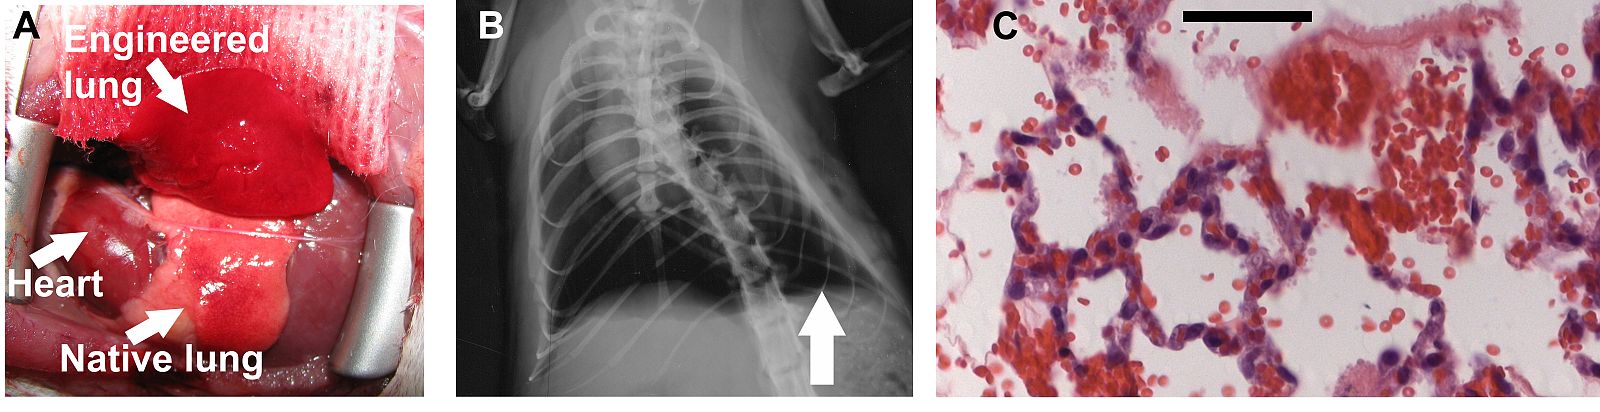

"Cuando trasplantamos por primera vez los pulmones bioartificiales y vi que funcionaban, que intercambiaban oxígeno y dióxido de carbono, me emocioné", relata a RTVE.esThomas Petersen, ingeniero de tejidos de la Universidad de Yale (EE.UU). Junto a su equipo han logrado implantar con éxito pulmones creados en el laboratorio en ratas. La revista 'Science' acaba de publicar los detalles de su investigación.

"Los ratones vivieron con los pulmones artificiales durante dos horas y la sangre salía de ellos con un 100% de saturación de oxígeno, un nivel muy bueno", apunta el científico.

Este andamiaje incluía la carcasa de pulmón, las principales vías respiratorias y el sistema vascular. Cuando lo consiguieron, inyectaron células de pulmones de feto de rata que habían cultivado en el laboratorio. A los ocho días, el pulmón de laboratorio tenía alveolos, microvasos sanguíneos y las pequeñas vías respiratorias que le faltaban. Estos nuevos tejidos fueron repobladas con las células cultivadas correspondientes.

A pesar de este gran avance hacia la creación de órganos a la carta, los científicos reconocen que aún hay mucho que mejorar en el pulmón para ratas. "Hay que minimizar la formación de coágulos en los vasos sanguíneos, y las fugas de componentes de la sangre a las vías respiratorias", señala Petersen. Y una vez alcanzado todo eso, "hay que probar a trasplantar en ratas los pulmones durante periodos más largos".